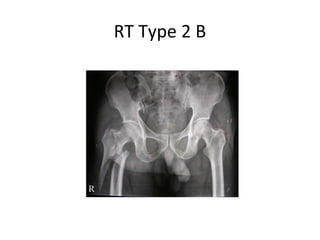

Russell-Taylor Classification

• Based on integrity of the piriformis fossa.

• Designed to guide treatment of intramedullary nails

using a piriformis fossa starting point.

Type I - intact piriformis fossa

A - lesser trochanter attached to proximal fragment

B - lesser trochanter detached from proximal fragment

Type II - fracture extends into piriformis fossa

A - stable posterior-medial buttress

B - comminution of lesser trochanter

RT Type 2 B